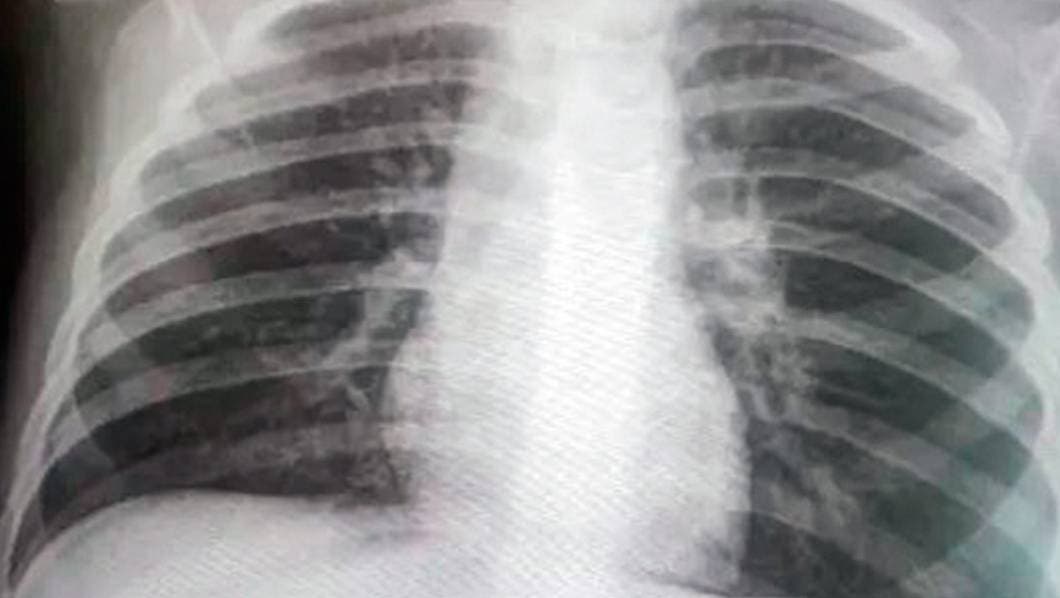

Cuernavaca, MORELOS.- Autoridades municipales indican que han aumentado los fallecimientos por “neumonías atípicas”, por lo que consideran que no coinciden las cifras de contagios por COVID-19 que informan autoridades de Salud estatal y federal.

Suben decesos por neumonías

“En el registro civil se han registrado muchas defunciones por neumonías atípicas o por cuestiones relacionadas; contabilizando sería la tercera causa de decesos que se registran actualmente”, declaró. iCumplen